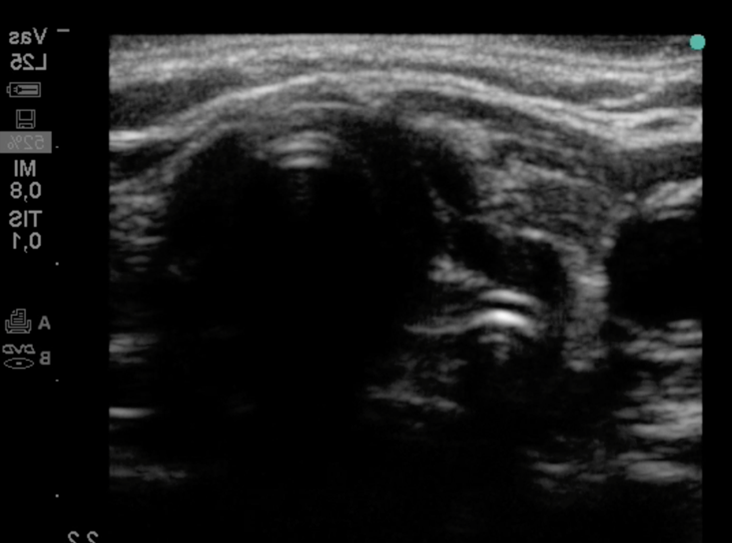

La siguiente imagen de ecografía corresponde a un control posintubación. ¿Ha sido exitosa esta intubación?